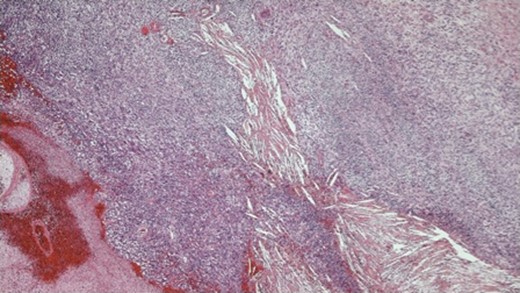

The histopathology demonstrated that the breast was partially replaced by a partly cystic and partly solid necrotic lesion. The cystic cavity contained blood clots. A microscopic examination showed an atypical undifferentiated spindle cell lesion with a fascicular architecture, pleomorphism and marked mitotic activity with areas of ulceration and necrosis (Figs 1 and 2). The initial set of immunostains performed showed that tumour cells were negative for cytokeratins (Fig. 3), S100 and LCA. The tumour cells showed diffuse and strong vimentin positivity (Fig. 4). Further immunocytochemical labelling showed weak expression of CD99, patchy strong expression of CD10 and patchy weak expression of smooth muscle actin. Cytokeratins (CAM 5.2) and EMA were expressed and there was no tumour-specific expression of CD34, desmin or myogenin. Fluorescent In-situ hybridization analysis failed to demonstrate evidence of a t(x:18) translocation using the LYS-SYT break apart probe. The diagnosis of a Grade 3 undifferentiated spindle cell sarcoma was made and although the tumour was reported to have a clear resection margin (5 mm) in most areas, the presence of necrosis and granulation tissue reaching the deep margin made the status of the margin uncertain.

Photomicrograph ×40 H&E; pleomorphic spindle cells in fascicles with several mitoses.